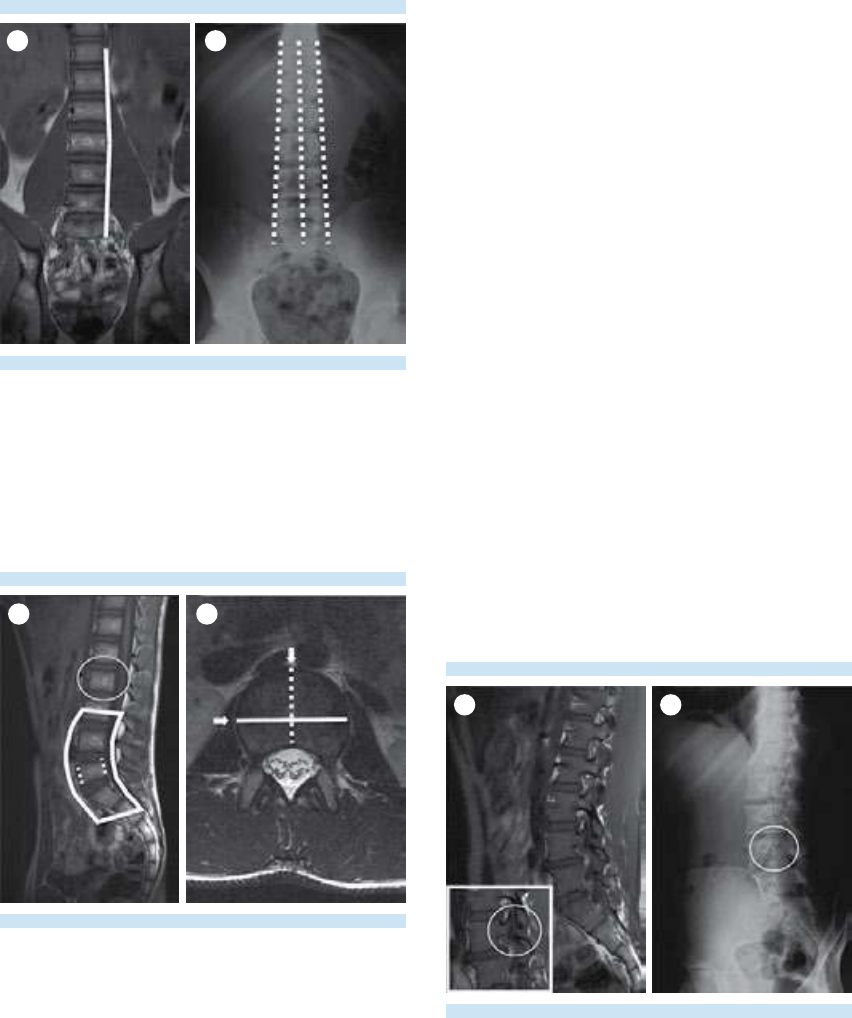

Los riñones se suelen observar en un estudio

rutinario de resonancia magnética de columna

lumbar, encontrándose con frecuencia diferen-

tes patologías. Así mismo, los incidentalomas

suprarrenales son frecuentes y no deben pasar

desapercibidos.

Las articulaciones sacroilíacas pueden verse de

forma rutinaria y es importante avaluar su sime-

tría y descartar cambios degenerativos u otras

alteraciones a este nivel.